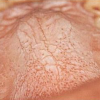

Lame lihhen on üks sagedasematest suu limaskesta muutustest. 70%-l patsientidest, kellel esinevad nahamuutused, on lihhenile tüüpilised muutused ka suu limaskestal. Seevastu suu lihhenit põdevatest patsientidest on nahamuutused ainult 30–40%-l. Enamik...